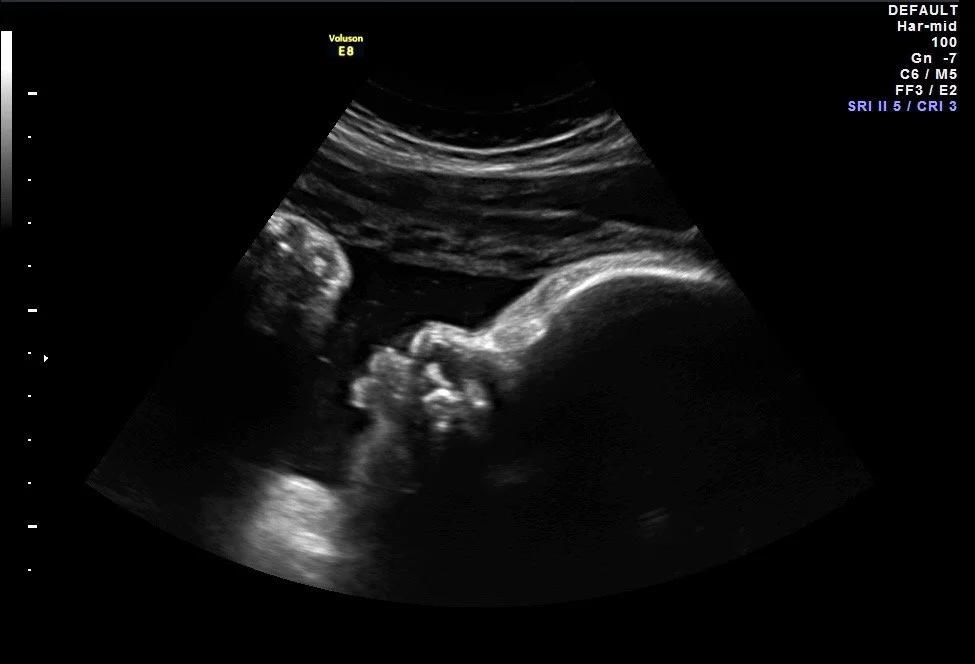

Este paquete es para familias a las que les encantaría visitarlo durante cada trimestre durante su embarazo. Esto incluye un primer vistazo (7-14 semanas), determinación de género (15-22 semanas), (2) sesiones 3D/4D/HD de 25 minutos recomendadas entre 28 y 36 semanas, álbumes digitales en cada visita, grabación de vídeo de cada sesión y un animal de latido del corazón de su elección. Ahorros de $160

Este paquete es para madres que visitan varias veces (mínimo 3 visitas) a lo largo de su viaje de embarazo. Incluye: sesión de 25 minutos del bebé en 2D/3D/4D/HD; álbum digital de todas las imágenes; más de 6 impresiones en blanco y negro; vídeo de toda la sesión; (1) unidad USB dada para traer de vuelta a cada sesión para documentar el desarrollo del bebé.